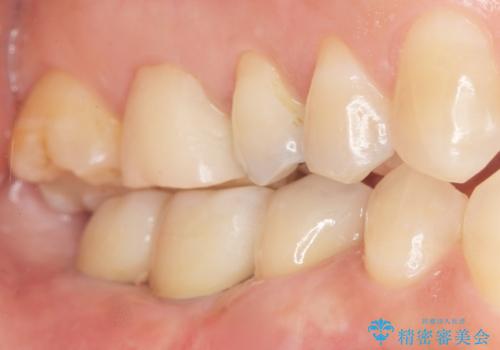

奥歯でしっかり噛むことができるようになり、喜んで頂けました。

セラミッククラウンの審美的な仕上がりにもご満足頂けました。

クラウンの種類:ベレッツァクラウン(右下76)、ジルコニアクラウン スタンダード(右下5)